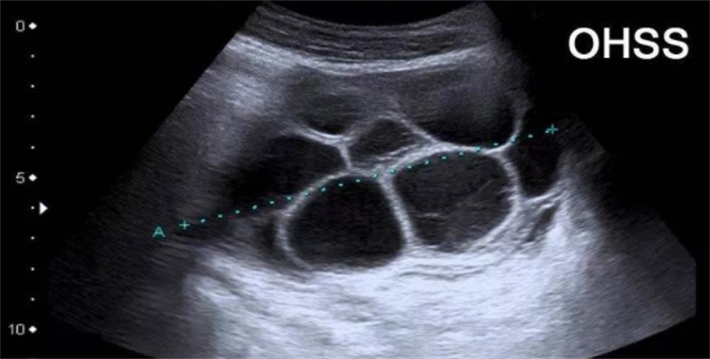

在取卵前使用Lupron时,能在短时间内激发LH峰,达到与HCG类似的促使卵泡成熟和排卵的效果。不过,Lupron与HCG触发针在使用上存在差异。一般来说,HCG的应用更为广泛,能有效促进大多数女性获取成熟优质卵子。而Lupron主要用于一些特殊情况,比如患有多囊卵巢综合征(PCOS)的女性。PCOS患者的卵巢对促排卵药物反应较为敏感,使用HCG触发可能会增加卵巢过度刺激综合征(OHSS)的风险,而Lupron能在一定程度上避免这种风险。

若取卵时间晚于36小时,卵子会逐渐老化。卵子老化后,其细胞膜的通透性会发生改变,影响精子的穿透和受精过程。老化卵子的细胞质中,线粒体等细胞器的功能也会下降,无法为胚胎发育提供足够的能量。此外,过晚取卵还会增加卵巢过度刺激综合征(OHSS)的发生几率。由于卵泡过度成熟,卵巢内的血管通透性增加,大量液体渗出到腹腔等部位,导致女性出现腹胀、腹水、胸水等症状,严重时还可能影响心肺功能,危及生命。